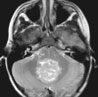

Traitement du médulloblastome du jeune enfant par chimiothérapie postopératoire seule

Le médulloblastome représente la tumeur primaire la plus fréquente du système nerveux chez l'enfant (13 à 28% des tumeurs cérébrales de l'enfant et 3,7% des tumeurs cérébrales). On compte 50 nouveaux cas chaque année avec un pic entre 3 et 8 ans et une prépondérance masculine. Le pronostic des jeunes enfants atteints de cette maladie est mauvais et les survivants présentent un risque élevé de déficit cognitif. Une équipe de chercheurs allemands a mené une étude évaluant le traitement de cette tumeur cérébrale par chimiothérapie postopératoire intensive seule. Les résultats de l’étude viennent d’être publiés dans le New England Journal of Medicine.